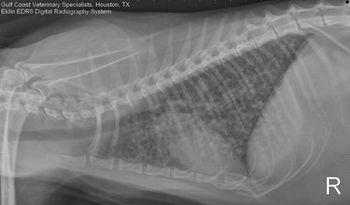

Image Quiz: Polyuria in a Pomeranian with a history of hair cycle arrest, Answer C